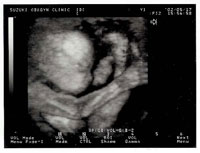

検診時に3Dエコーも録画できます。